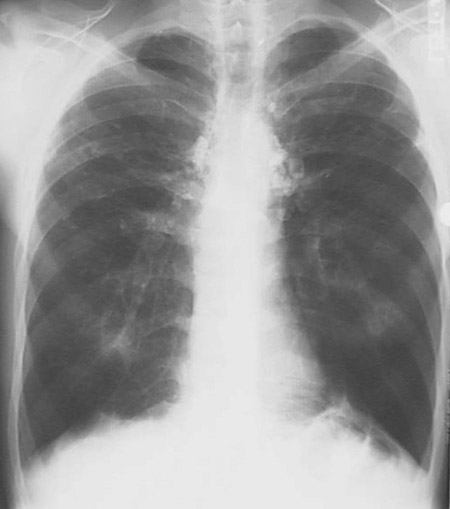

This chest radiograph demonstrates an silicotic nodules of varying sizes scattered throughout the lung, resulting in an interstitial lung disease.